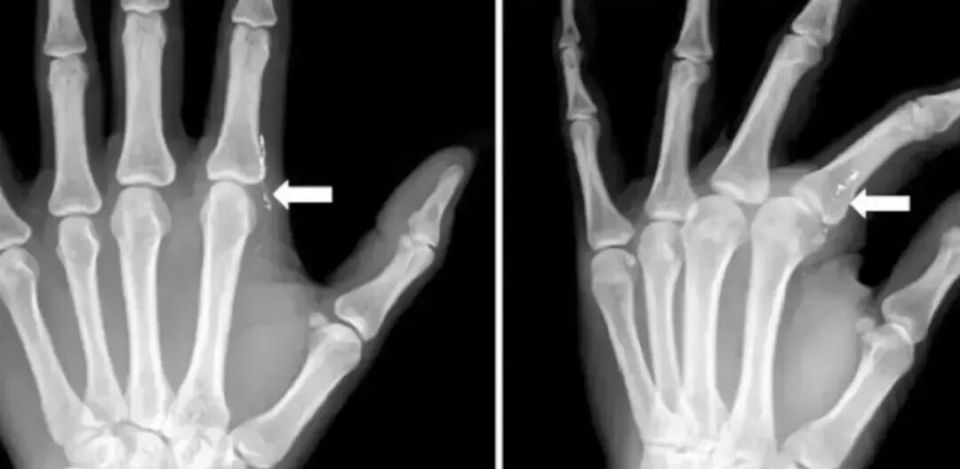

J Hand Surg Asian Pac 曾颁发 过如许一个病例[1]一名 42 岁的妈妈去看病,以为「左食指有异物感」。

大夫追问病史了解 到,她在 1 个月前在给女儿量体温时,不小心打碎水银温度计。清算体温计碎片的时间,左手指被刺伤,其时以为没有大碍,就没有就诊。

大夫发现,患者左手手指有肉芽构造,检验血液、尿液后发现,有汞中毒的迹象。

左食指第二掌趾关节桡侧疼痛

图片泉源:文献[1]

X 片可见皮下线状高密度影